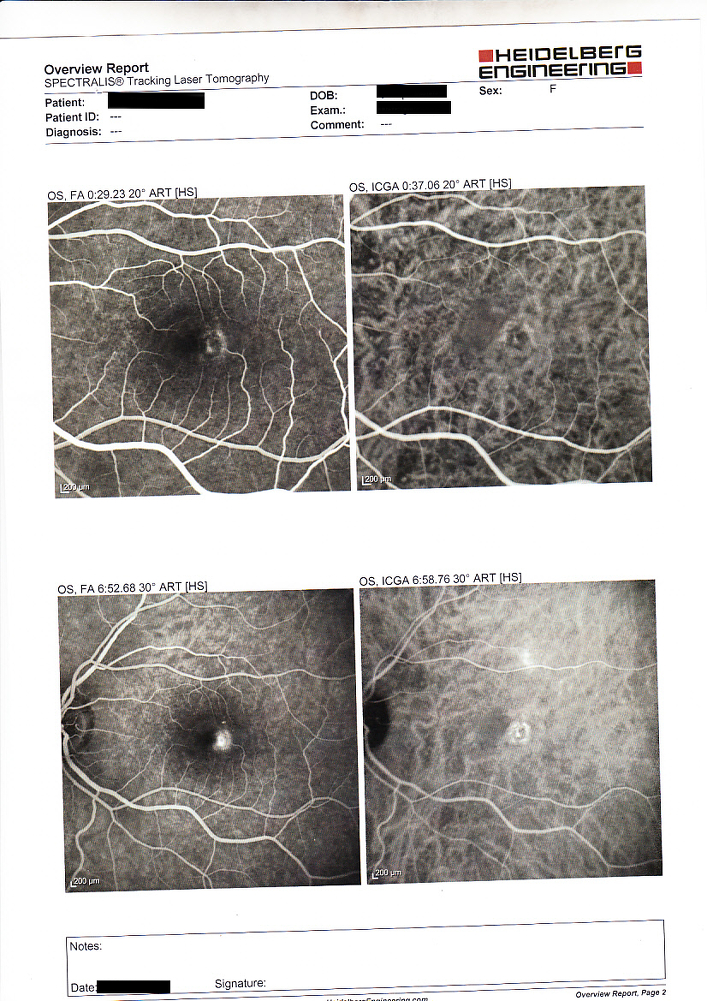

Effettuato OCT (vedi allegato): nell'occhio sinistro si evidenzia un distacco sieroso maculare

Effettuata fluorangiografia (vedi allegato): nell'occhio sinistro si evidenzia una membrana neovascolare sottoretinica maculare

Questo caso poteva essere di difficile interpretazione all'inizio per l'assenza di emorragie retiniche maculari che indicassero la presenza di una neovascolarizzazione e per l'evidenza all'OCT di un distacco sieroso che poteva essere anche di altra natura, la fluorangiografia ha permesso di evidenziare l'esatta causa.

Questo ci dimostra come OCT e fluorangiografia siano esami entrambi importanti e con informazioni complementari e spesso è necessario effettuarli entrambi per un corretto studio delle maculopatie.